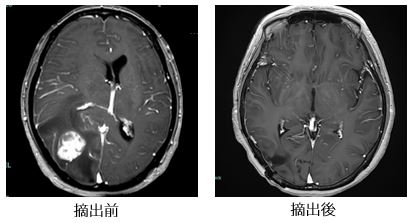

脳のさまざまな部位に発生する異常血管の塊です。出血を繰り返して脳の圧迫や刺激による神経症状(てんかん、麻痺、構語障害、嚥下障害、頭痛、めまい、複視など)の悪化を来たすことがありあす。出血を繰り返し神経症状が悪化する場合やてんかんの原因になっている場合には摘出術を行います。